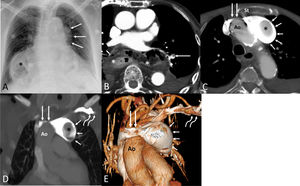

(A) Anteroposterior chest radiograph shows an abnormal left mediastinal contour (arrows). Note a large hiatal hernia (asterisk). (B) Axial thoracic CT image shows a non-occlusive filling defect involving a segmental pulmonary artery (arrow); note the large hiatal hernia (asterisks). (C) Axial thoracic CT image demonstrates a narrowed left innominate vein (long arrows) running between the sternum (St) and the ascending aorta (Ao), a saccular aneurysm of the left innominate vein (short arrows), and a large filling defect within the aneurysm (asterisk). (D) Coronal thoracic CT image shows the compressed left innominate vein (long straight arrows) by the ascending aorta (Ao) and the retrograde aneurysmal dilatation of the left innominate vein (short arrows); note the intra-aneurysmal thrombus (asterisk) and the normal-looking left subclavian vein (curved arrows). (E) 3D reconstruction CT image shows the stenotic left innominate vein (long straight arrows) compressed by the ascending aorta (Ao), the retrograde dilatation of the left innominate vein (short arrows), and the normal-looking left subclavian vein (curved arrows).

A 102-year-old patient presented to our hospital with shortness of breath. A chest radiograph showed an abnormal left mediastinal contour (Fig. 1A). A contrast-enhanced thoracic CT demonstrated a low-burden pulmonary embolism (Fig. 1B) as well as a narrowed aortosternal space resulting in a severe left innominate vein (LIV) compression and a large retrograde partially-thrombosed aneurysm of the LIV (Fig. 1C–E). Following consultation with the surgical team, it was decided to treat the patient conservatively (anticoagulant therapy). Isolated innominate vein aneurysms (IVAs) are very rare, with less than 36 cases reported in the literature [1]. The etiology of IVAs remains undetermined, although congenital malformations, trauma, vascular interventions (including intravascular devices), and inflammation/infection have been implicated. Most IVAs are incidentally detected on imaging, but some patients may experience symptoms due to rupture, thrombus formation or pulmonary embolism. The use of intravenous contrast is particularly important to avoid confusing an IVA with a solid mediastinal mass. Treatment options for IVAs include conventional open surgical repair and less invasive endovascular approaches, with the choice of technique guided by aneurysm morphology, symptomatology, and patient-specific risk factors. In our case, we speculate that the narrow aortosternal space may be the most plausible cause of chronic LIV stenosis and retrograde dilatation of the LIV with intra-aneurysmal thrombus formation.